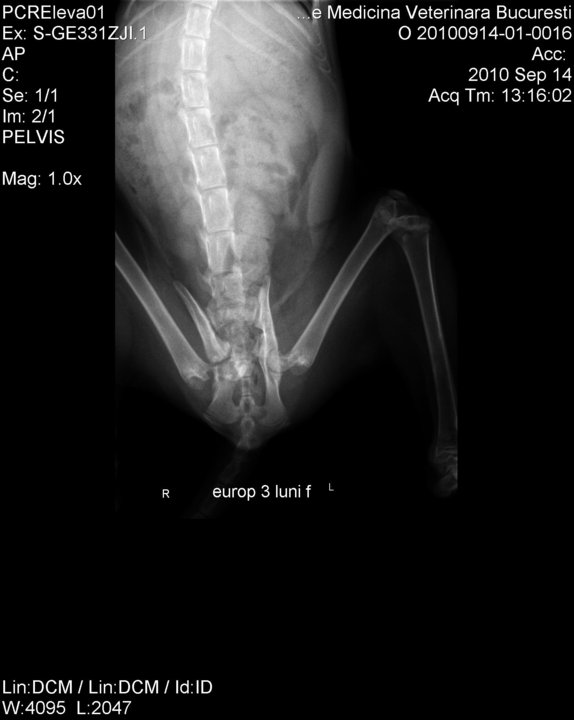

And this is after the operations, recuperating at the vet’s office.